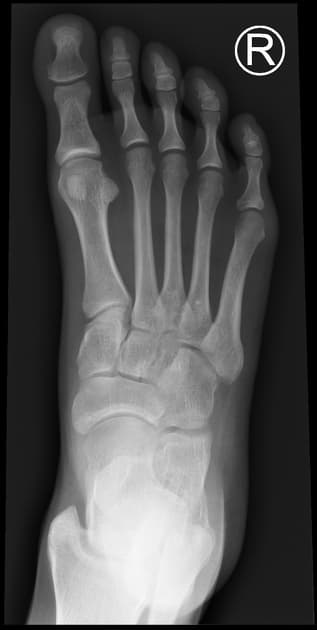

Foot Projections

Foot Projections Patient Preparation Explain the procedure to the patient.. Remove shoes, socks, and any metallic objects from the area of interest.. Ensure the foot is clean and comfortable.. Use lead shielding as appropriate.. --- BASIC PROJECTIONS Dorsoplantar (AP) Projection — Foot. ...

Read more →